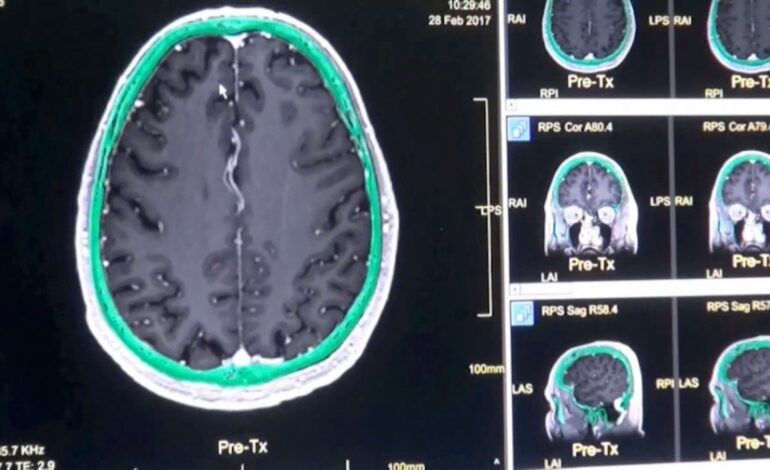

los investigadores comparó los cerebros de 3.802 personas de cero a noventa años utilizando datos de resonancias magnéticas de difusión, creando mapas de conexiones neuronales. En este proceso se siguió el movimiento de las moléculas de agua a través del tejido cerebral, considerando la sustancia blanca del órgano (la parte interna) y la materia gris (la corteza externa).